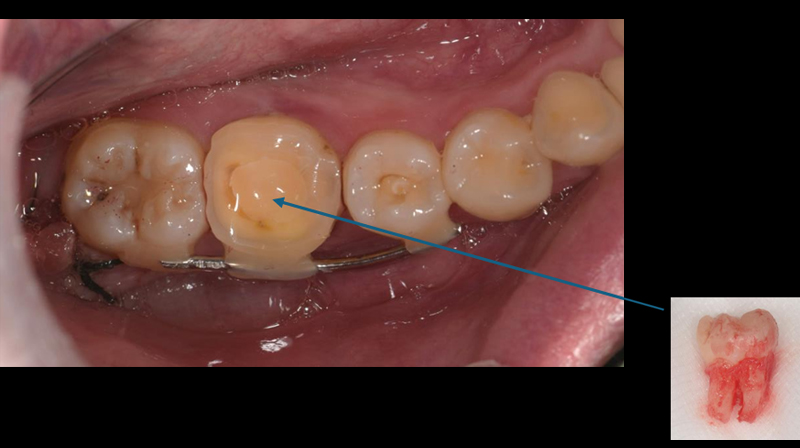

拔除智齒,固定至第一大臼齒缺牙區域

智齒固定

治療演進